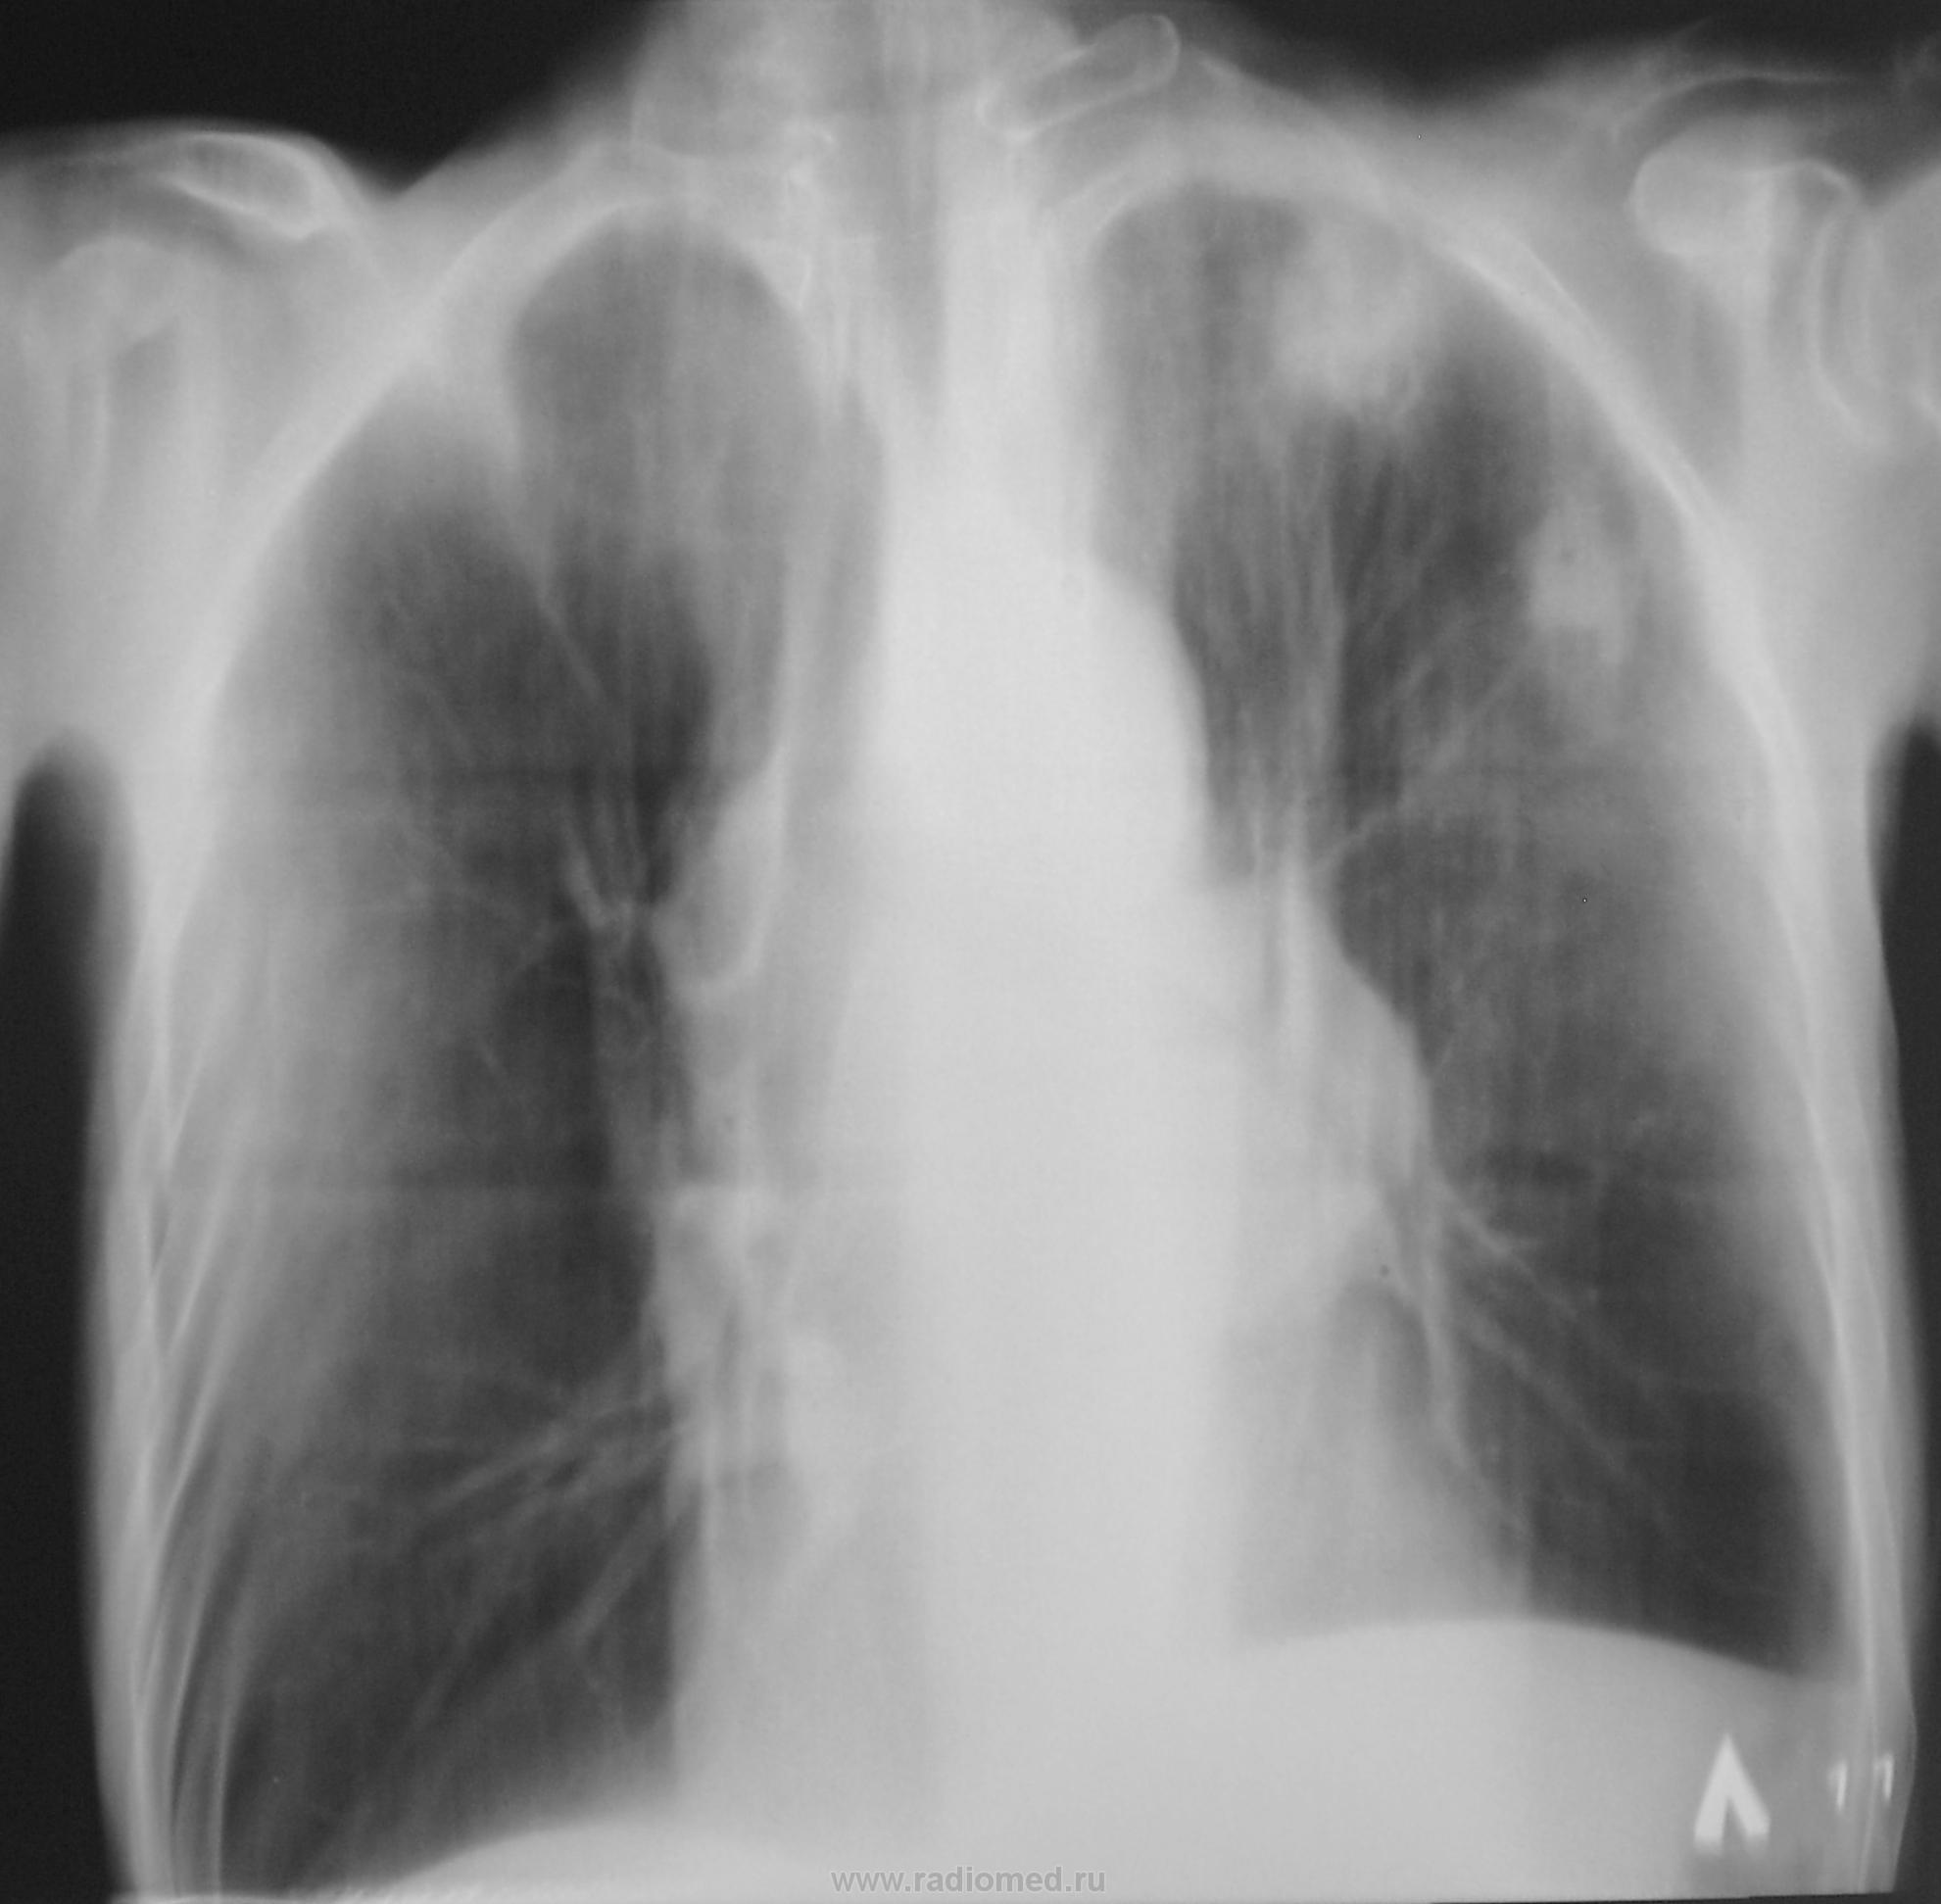

Направлен был, как "клиническое излечение".

из нас прав! Здесь  палочки Коха врачам не помощники. Нужны предшествуюшие рентгенограммы.

После этого исследования мокроту пообследовали..., и "балеринок" нашли...

А, помеченные Вами "распадики", на экране профессионального монитора (томограммы) хорошо были видны. Я не стал выставлять все срезы, выставил только оптимальный.